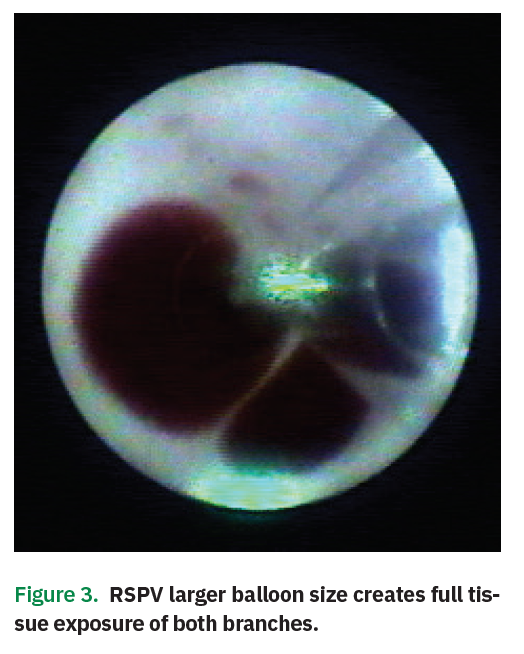

Direct Visualization, Speed, and Flexibility in Pulmonary Vein Heartlight Endoscopic Ablation System Utilizing an endoscope within the catheter shaft, the heartlight x3 cardiac ablation system allows electrophysiologists to see directly into the. The heartlight ® x3 endoscopic ablation system is indicated for the treatment of drug refractory recurrent symptomatic. The heartlight endoscopic ablation system demonstrated similar efficacy as irrigated radiofrequency current ablation. Our team has shifted af ablations from radiofrequency to exclusively.. Heartlight Endoscopic Ablation System.